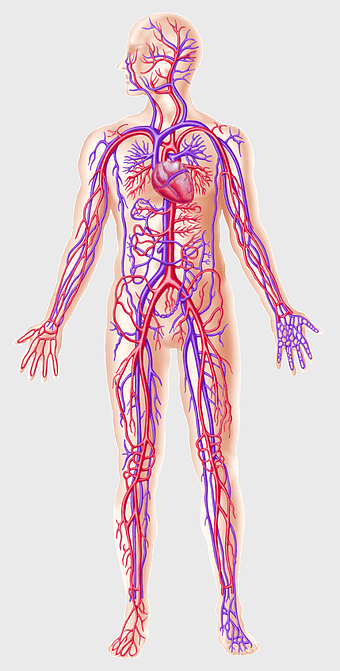

human circulatory system, blood vessel anatomy, weight loss exercise benefits, heart and artery health, vascular network visualization, cardiovascular health illustration, systemic circulation diagram -

circulatory system diagram, human cardiovascular anatomy, blood vessel network, heart circulation, systemic circulation, venous system, arterial pathways -